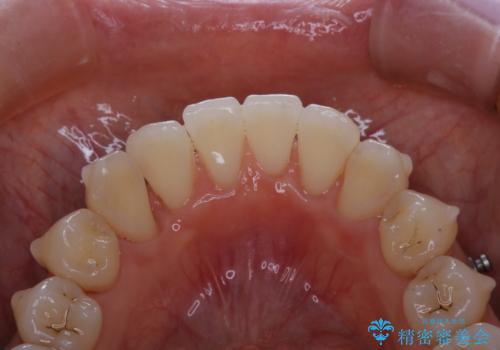

インビザライン中の方 結婚式前にPMTCでステインの除去

- インビザラインでの矯正治療中ですが、結婚式があるため全体の着色・ステインを綺麗にしたいとのことでした。PMTC60分コースを行いました。

PMTC(保険外治療)は、毎日の歯磨きで落としきれない汚れや、コーヒ、紅茶・タバコのヤニなどの着色も除去します。目には見えない歯と歯の間・歯肉の境目・インビザライン中はアタッチメント周囲などに残っているプラーク(歯垢)もしっかり取り除きます。PMTCでは専門的な機械や材料を使用して、徹底的に汚れを除去するため、虫歯・歯周病・口臭予防などにつながります。

またPMTCを行うことで、ご自身本来の歯の色になり自然な明るさになります。